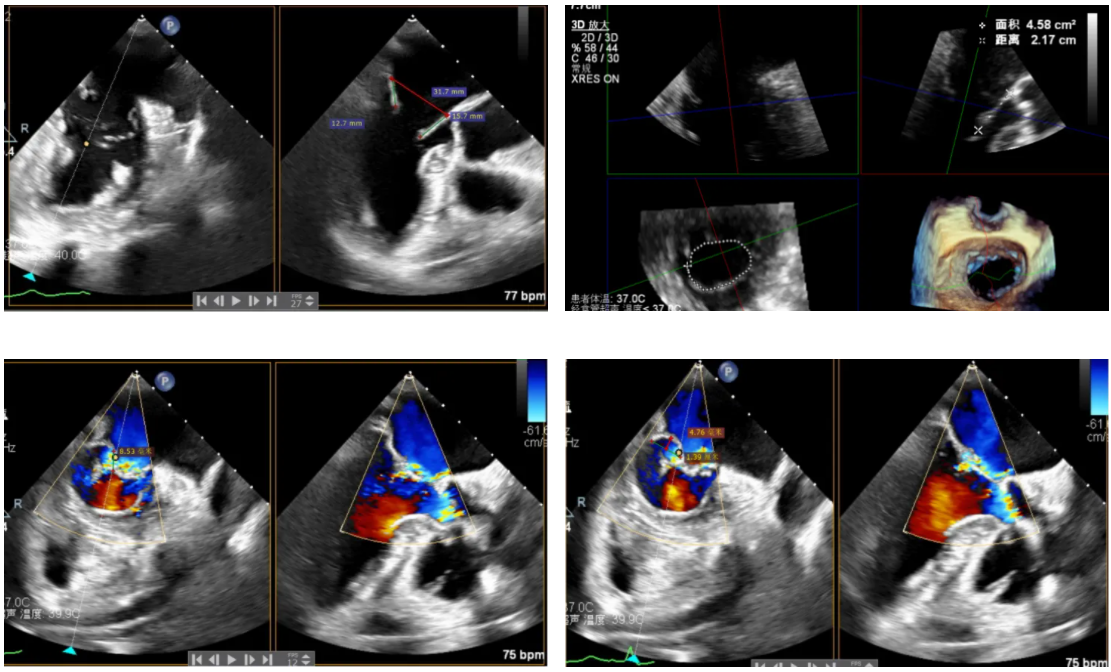

患者为原发性二尖瓣反流(DMR),收缩期可见二尖瓣反流信号,反流位于 2 偏 3 区,基线期二尖瓣反流程度4+。

前叶长度 15.7mm,后叶长度 12.7mm,后叶脱垂宽度13.9mm,脱垂高度4.76mm, 瓣环直径37.1mm,VC:4*7mm,  MVA约4cm² 。瓣叶质地较差,腱索断裂、后瓣叶脱垂。

术前超声